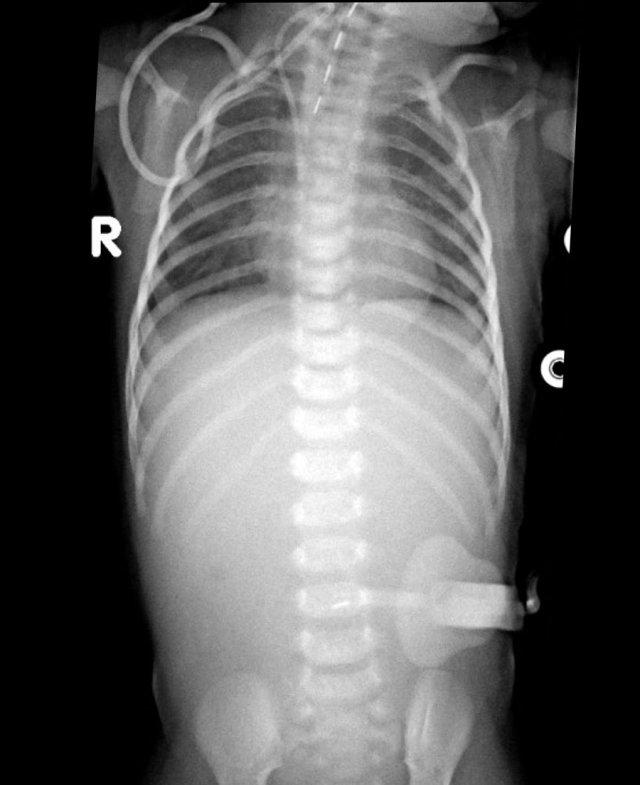

Các dấu hiệu bao gồm:

- Nhiều quai ruột non giãn cho thấy tắc nghẽn đoạn thấp

- Thụt tháo cản quang cho thấy khẩu kính trực tràng nhỏ hơn so với khẩu kính đại tràng sigma

- Trực tràng có hình ảnh co thắt dạng răng cưa.

Chẩn đoán:

Bệnh Hirschsprung đoạn ngắn.